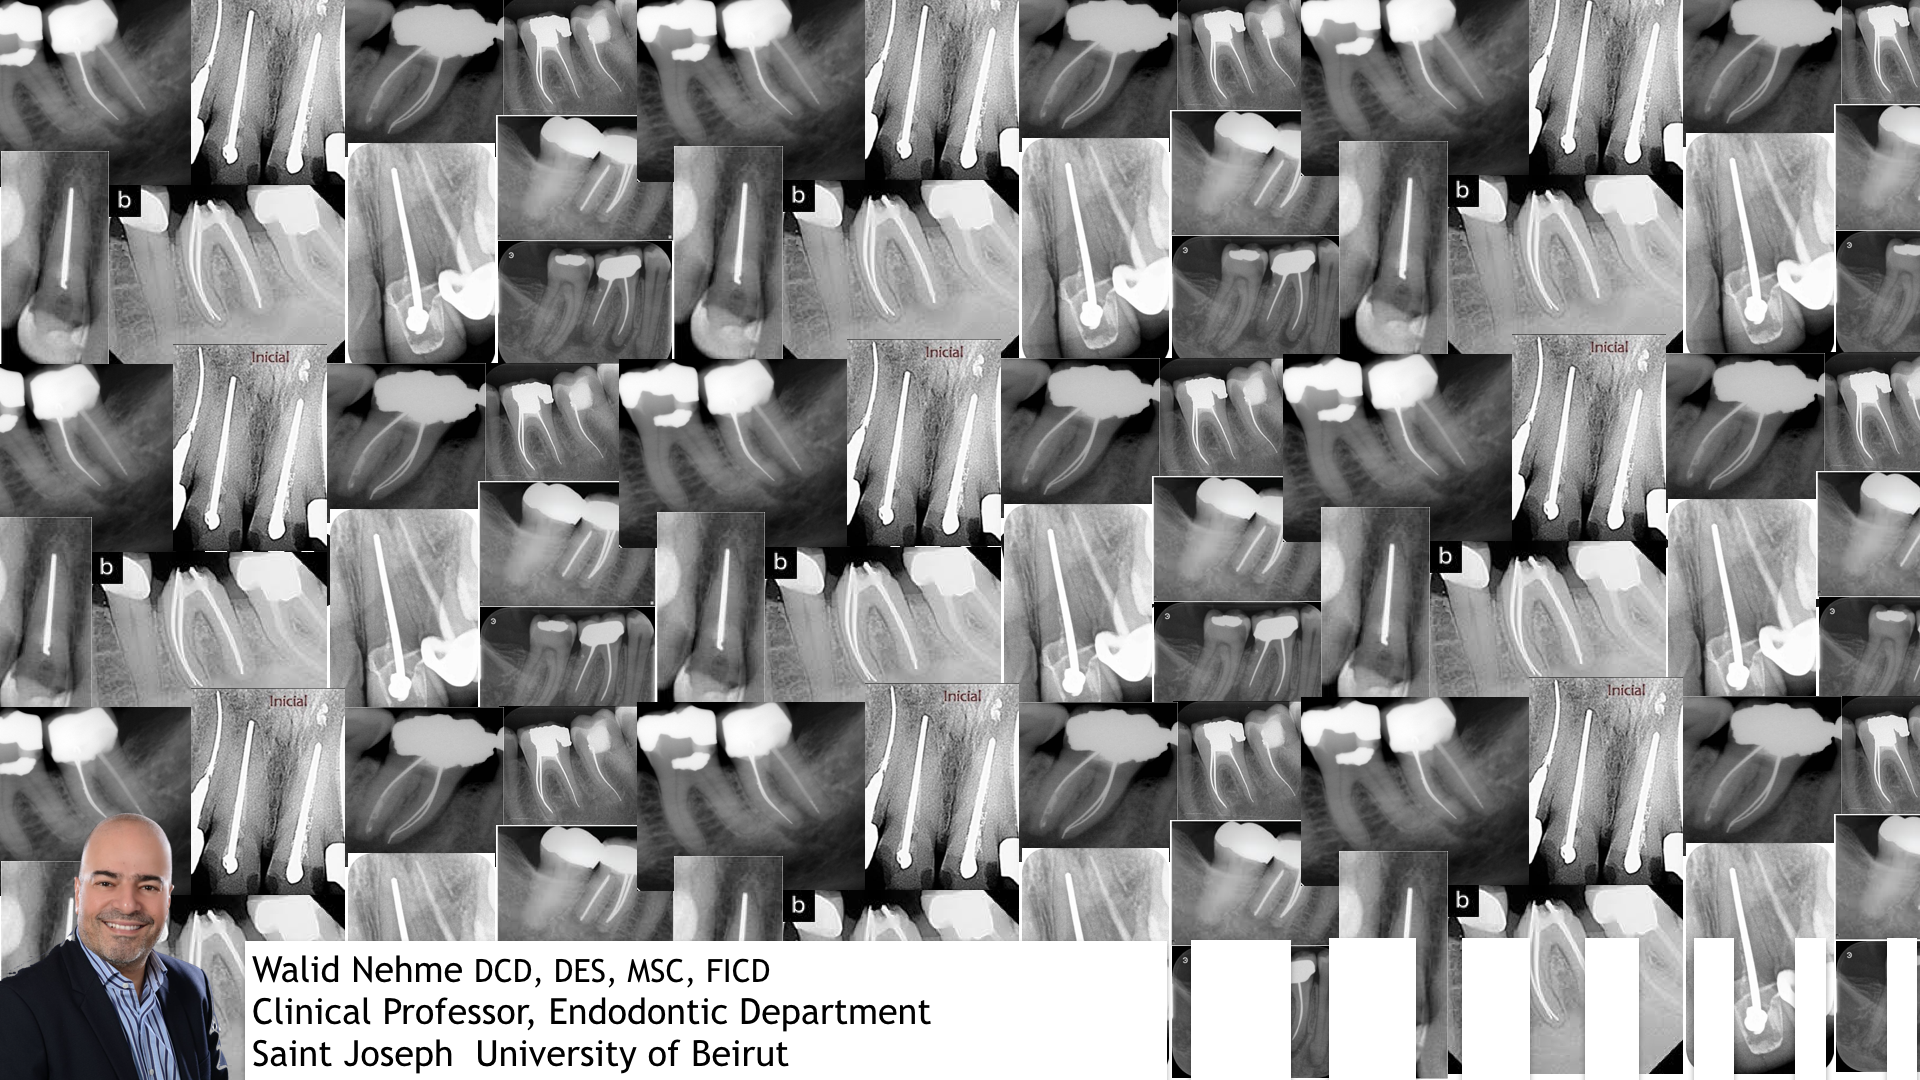

This webinar helps us understand the complexity of the root canal system,adjusting the tools according to specific anatomical situation, dealing with curvatures, supplementary canals, calcified system and large foramina and introduces us to new irrigation tools

Video length : 27:39 min